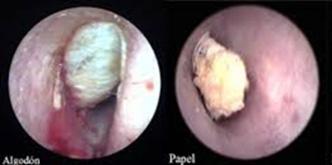

A la otoscopía el proceso inflamatorio es menor comparado con la otitis externa difusa, los crecimientos micóticos se verán como finos filamentos de hongos y esporas que se asemejan al moho que crece en los alimentos en mal estado. Las esporas de A. niger parecen un polvo fino de carbón rociado en el canal auditivo. El Aspergillus también puede parecerse a un periódico húmedo o papel secante. Las infecciones por cándida generalmente se asocian con un material blando, blanco, parecido a las sebáceas que puede llenar el canal auditivo en casos graves. Una pseudomembranosa a menudo recubre el canal auditivo que, cuando se retira, revela una membrana granular friable subyacente.

Figura 17. Otitis externa micótica